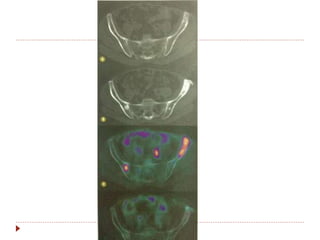

Avaliação de resposta com PET-CT

 Utilizar sempre o mesmo aparelho.

 SUV (standart uptake value).

 Diferencia tumor viável de necrose/fibrose.

 PERSIST 1.0

 Validade perante o RECIST: lesões novas

(confirmadas com TC) e não valor de captação.

Avaliação de respostacom PET-CT  Utilizar sempre o mesmo aparelho.  SUV (standart uptake value).  Diferencia tumor viável de necrose/fibrose.  PERSIST 1.0  Validade perante o RECIST: lesões novas (confirmadas com TC) e não valor de captação.